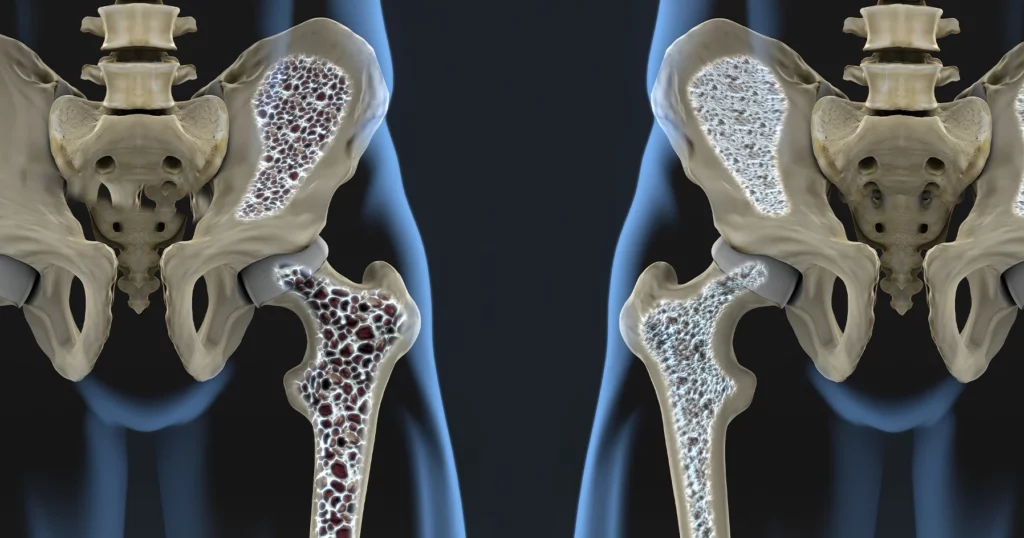

Avem o descoperire majoră în domeniul osteoporozei. O echipă de cercetători din Germania anunță rezultate promițătoare care ar putea revoluționa tratamentul acestei afecțiuni osoase. Cercetările au arătat că activarea unui receptor specific din organism, denumit GPR133, conduce la creșterea densității osoase și la regenerarea țesutului afectat.

Studiile au demonstrat că receptorul GPR133 joacă un rol crucial în controlul rezistenței oaselor. Activarea acestui receptor, în cadrul experimentelor pe animale, a dus la rezultate spectaculoase. S-a observat o creștere semnificativă a densității osoase, dar și o regenerare a țesutului osos deteriorat. Aceste descoperiri sugerează că GPR133 ar putea fi o țintă terapeutică eficientă pentru tratarea osteoporozei, o boală care afectează milioane de oameni la nivel global. Cercetările au fost efectuate în Germania, iar datele preliminare sunt îmbucurătoare.

Osteoporoza este o boală caracterizată prin scăderea densității minerale osoase și deteriorarea arhitecturii osoase, ducând la fragilitate crescută și risc ridicat de fracturi. Tratamentele actuale se concentrează, în principal, pe încetinirea pierderii osoase sau pe stimularea formării de țesut osos nou. Descoperirea rolului GPR133 oferă o nouă perspectivă, deschizând calea spre abordări terapeutice mai eficiente și mai specifice.